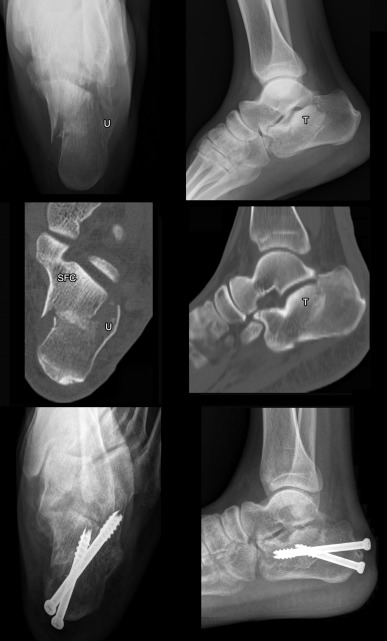

The fractures of subtype A1 and A3 were reduced by percutaneous pin of avulsion and bending fragments for restoring abnormal fracture parameters. Avulsion and bending fragments were fixed to calcaneal body by percutaneous screws. Then, spontaneous reduction of posterior subtalar joint including calcaneal morphology and alignment were obtained (Fig. 3 , Table 2 ).

Fig. 3

Fig. 3.

Subtype A1 intra-articular calcaneal fracture, calcaneal radiographs showed burst of lateral calcaneal wall (U) and bending fracture fragment (E) created incongruent posterior subtalar joint (2 pictures above). CT images showed that subtype A1 comprised type A sustentacular fragment (SFA) and entire posterior calcaneal facet (PCF) had intact articular surface (I) and associated with bending fragment of calcaneal body by its articular surface was anterior surface of the bending fragment (2 pictures middle). Percutaneous reduction and 2 screw fixations of the bending fragment were performed (2 pictures below). Pre- and postoperative calcaneal fracture scores improved from 8 to 1 points.